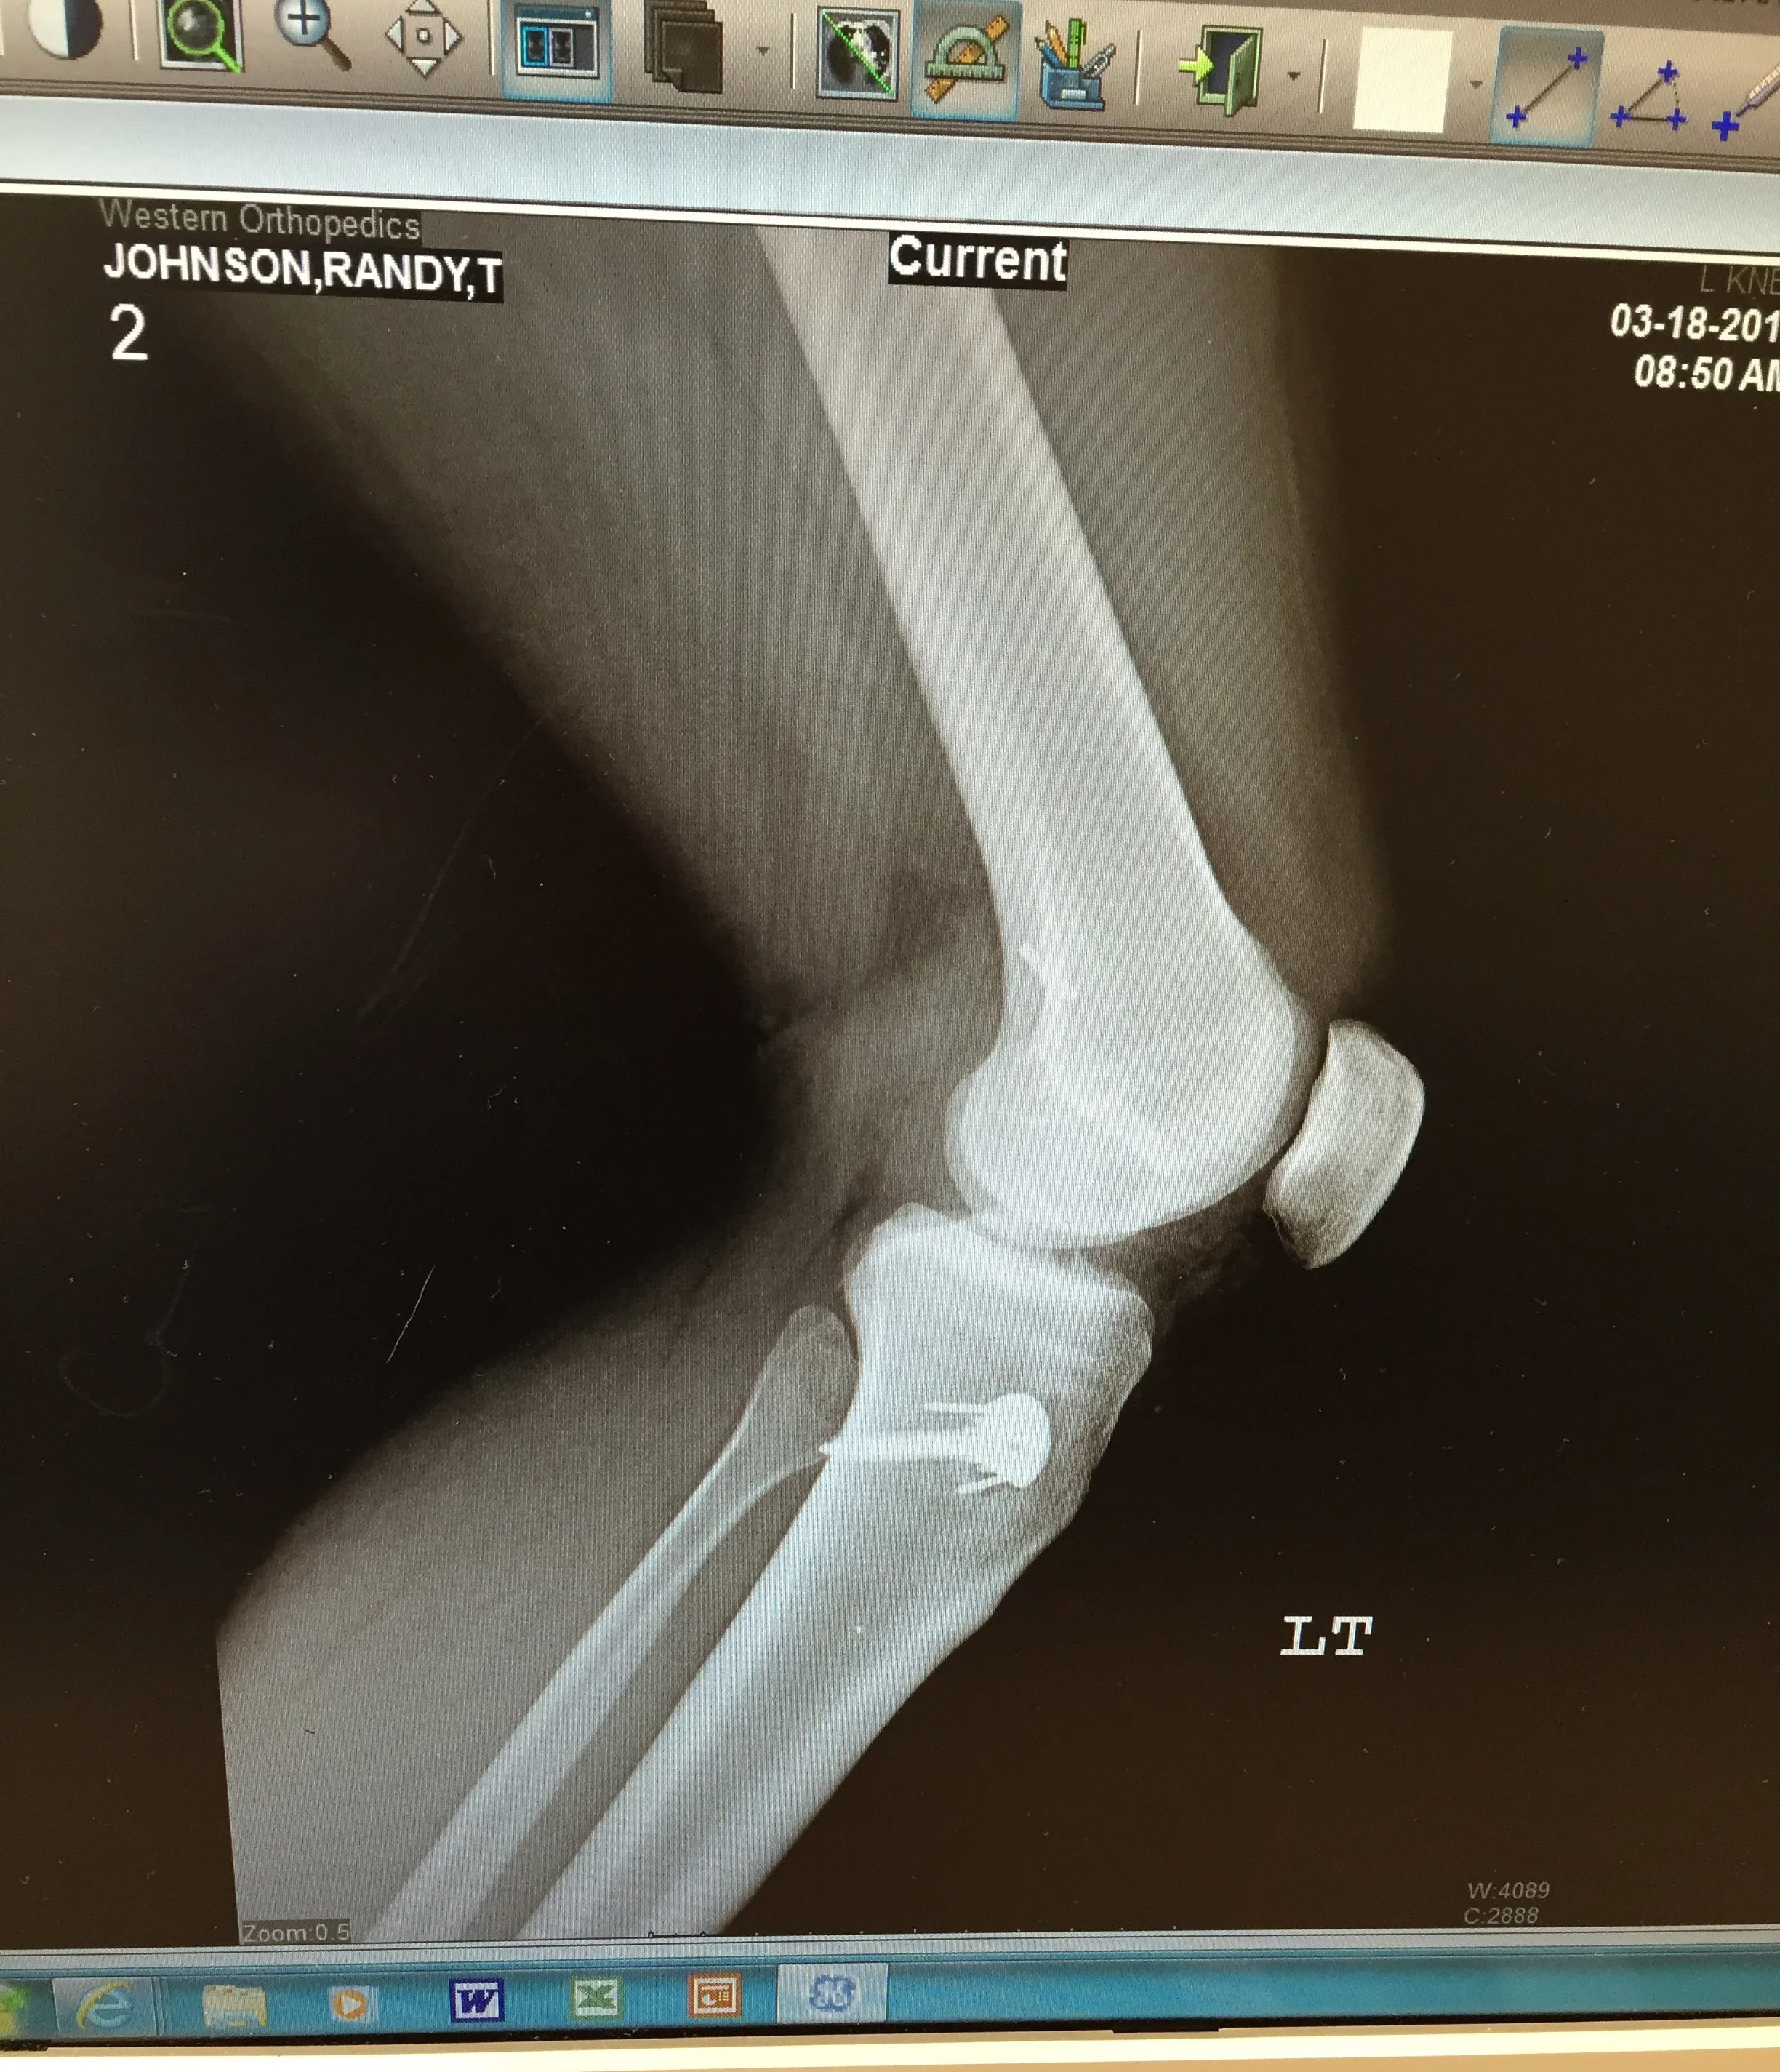

Then I tore my ACL, MCL, meniscus, and rotator cuff in a freak ski fall and all of a sudden my options were limited.

Post-surgery x-ray of my new hardware.

I had feared this moment for many years. I couldn't imagine a winter in Colorado without skiing. It seemed inevitable though--I ski hard and I ski fast, like, as fast as possible. But I remained confident as I stayed in shape and limited my recklessness and the risks I took. I dreaded missing summer because of volleyball and softball, and I dreaded missing winter because skiing was everything. Now I was forced to miss out on both as I rehabbed. No softball, no volleyball, no skiing, and worst of all, no hiking.